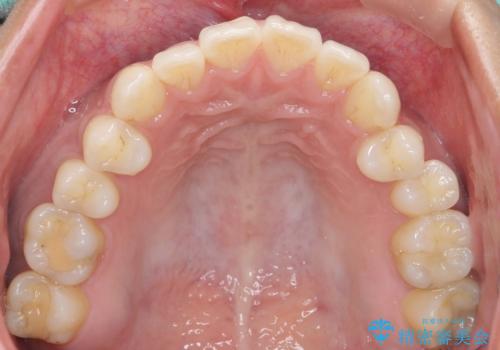

精査したところ、奥歯に充填された保険内のコンポジットレジンの適合が悪いことにより、汚れがたまりやすい状態でした。

不適合なレジンを除去し、セラミックインレーによる治療を行いました。(右上76左上67右下7の計5本)

インレーの種類:セラミックインレー e-max press